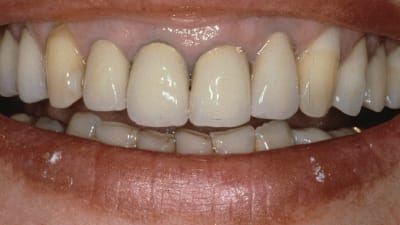

Case Report The Team Approach to Esthetic Immediate Implant Placement Bobby L. Butler, DDS, Greggory A. Kinzer, DDS, MSD October 01, 2012 12 min read

Case Report Principles of Esthetics Using All the Members of the Dental Team Ronald E. Goldstein, DDS October 01, 2012 17 min read